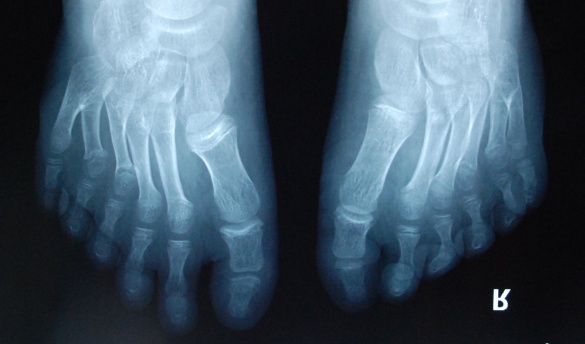

廈門眼科中心小兒眼科修陽暉博士在日常的診療過程中就接診了不少這樣的的特殊家庭,讓其尤為印象深刻的就是一年前接診的BBS綜合征患者。當(dāng)時(shí)來院就診的是一對親兄弟,之前已在多家醫(yī)院做過檢查,因其均有較大散光和斜視,肉眼下眼底檢查未見異常,故外院均診斷為弱視,這也符合眼科門診常規(guī)的診斷邏輯與思維。但由于兄弟倆均有智力發(fā)育遲緩、特殊面容及四肢均有六指和六趾的特異體征引起了修陽暉博士的警覺:會不會是一種特殊遺傳性疾病或綜合征?后續(xù)的檢查結(jié)果進(jìn)一步證實(shí)了修陽暉博士的懷疑---患兒均有夜盲,ERG、VEP及OCT檢查顯示雙眼的視網(wǎng)膜神經(jīng)上皮層結(jié)構(gòu)及功能均明顯異常。由于之前未遇到此種病例,修陽暉博士在診斷一欄寫下視網(wǎng)膜色素變性并打上了個(gè)問號,同時(shí)留下了病人的聯(lián)系方式。

BBS綜合征(Bardet-Biedl綜合征)是一種主要累及纖毛結(jié)構(gòu)與功能的罕見常染色體隱性遺傳性疾病。纖毛分布于哺乳動(dòng)物體內(nèi)的大多數(shù)細(xì)胞,它是一種廣泛存在于各種細(xì)胞表面的細(xì)胞器,體型微小但結(jié)構(gòu)復(fù)雜、作用強(qiáng)大,能感知細(xì)胞外機(jī)械和化學(xué)信號變化并協(xié)助其轉(zhuǎn)導(dǎo)到細(xì)胞內(nèi)部從而引起細(xì)胞應(yīng)答。高等動(dòng)物的視覺、觸覺、嗅覺、聽覺的傳遞都依賴于體內(nèi)外正常的纖毛結(jié)構(gòu)和功能。因此BBS綜合征常累及全身多個(gè)系統(tǒng)和器官,在臨床上主要表現(xiàn)為:視網(wǎng)膜色素變性、智力發(fā)育異常、向心性肥胖、多指(趾)、性腺發(fā)育異常、腎臟異常。除此之外還有許多諸如:語言發(fā)育障礙、聽力異常、嗅覺異常、斜視、白內(nèi)障、散光、牙齒發(fā)育異常、短指(趾)、并指(趾)、肝纖維化、糖尿病、高血壓等表現(xiàn)。